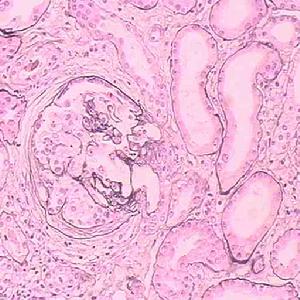

4.瀰漫性增生性腎小球腎炎型(WHOⅣ型)最嚴重而常見,約占半數以上。光鏡下幾乎所有的腎小球均有嚴重的改變,表現為系膜細胞和內皮細胞增生,白細胞聚集,許多細胞呈退行性改變,亦可有系膜細胞插入到基膜與內皮細胞之間,可有新月體形成。本型可出現“鐵絲圈樣病損及蘇木素小體,常提示狼瘡性腎炎的診斷。此外,可出現透明血栓,免疫螢光檢查可見腎小球所有區域IgG、IgM、IgA、C1q、C3、C4、C5-9,少數可有IgE呈顆粒狀沉積,特別是內皮下。電鏡下見顯著的電子緻密物沉積,主要見於內皮下及系膜區。